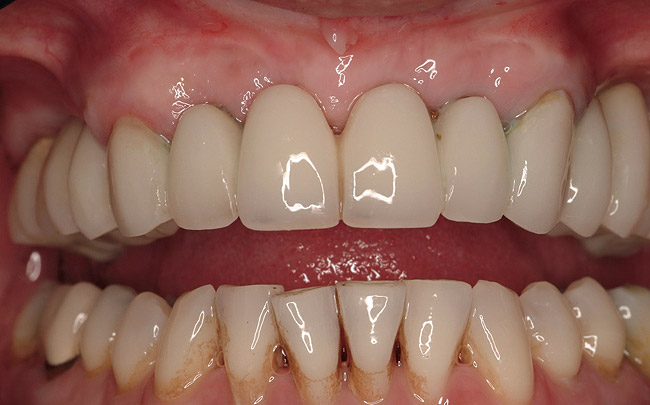

Figure 3  Pre-extraction situation. Tooth Nos. 24 and 25 were planned for extraction, and simultaneous ridge augmentation was planned. Implant placement in these two positions at the conclusion of active tooth movement was also planned.

Figure 3